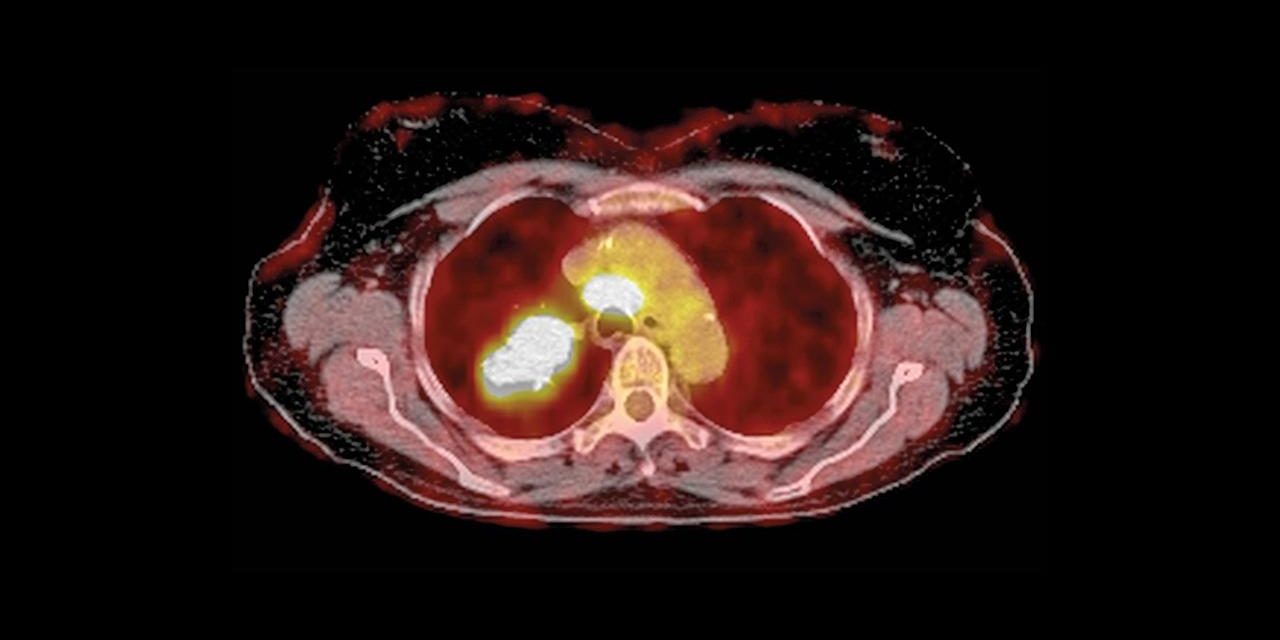

Cantley’s lab and collaborators found that large doses of vitamin C did indeed kill cultured colon cancer cells with BRAF or KRAS mutations by raising free radical levels, which in turn inactivate an enzyme needed to metabolize glucose, depriving the cells of energy. Then they gave daily high dose injections—equivalent to a person eating 300 oranges—to mice engineered to develop KRAS-driven colon tumors. The mice developed fewer and smaller colon tumors compared with control mice.

Cantley hopes to soon start clinical trials that will select cancer patients based on KRAS or BRAFmutations and possibly GLUT1 status. His group’s new study “tells you who should get the drug and who shouldn’t,” he says. Cancer geneticist Bert Vogelstein of Johns Hopkins University, in whose lab Yun noticed the GLUT1 connection, is excited about vitamin C therapy, not only as a possible treatment for KRAS-mutated colon tumors, which make up about 40% of all colon cancers, but also for pancreatic cancer, a typically lethal cancer driven by KRAS. “No KRAS-targeted therapeutics have emerged despite decades of effort and hundreds of millions of dollars [spent] by both industry and academia,” Vogelstein says.